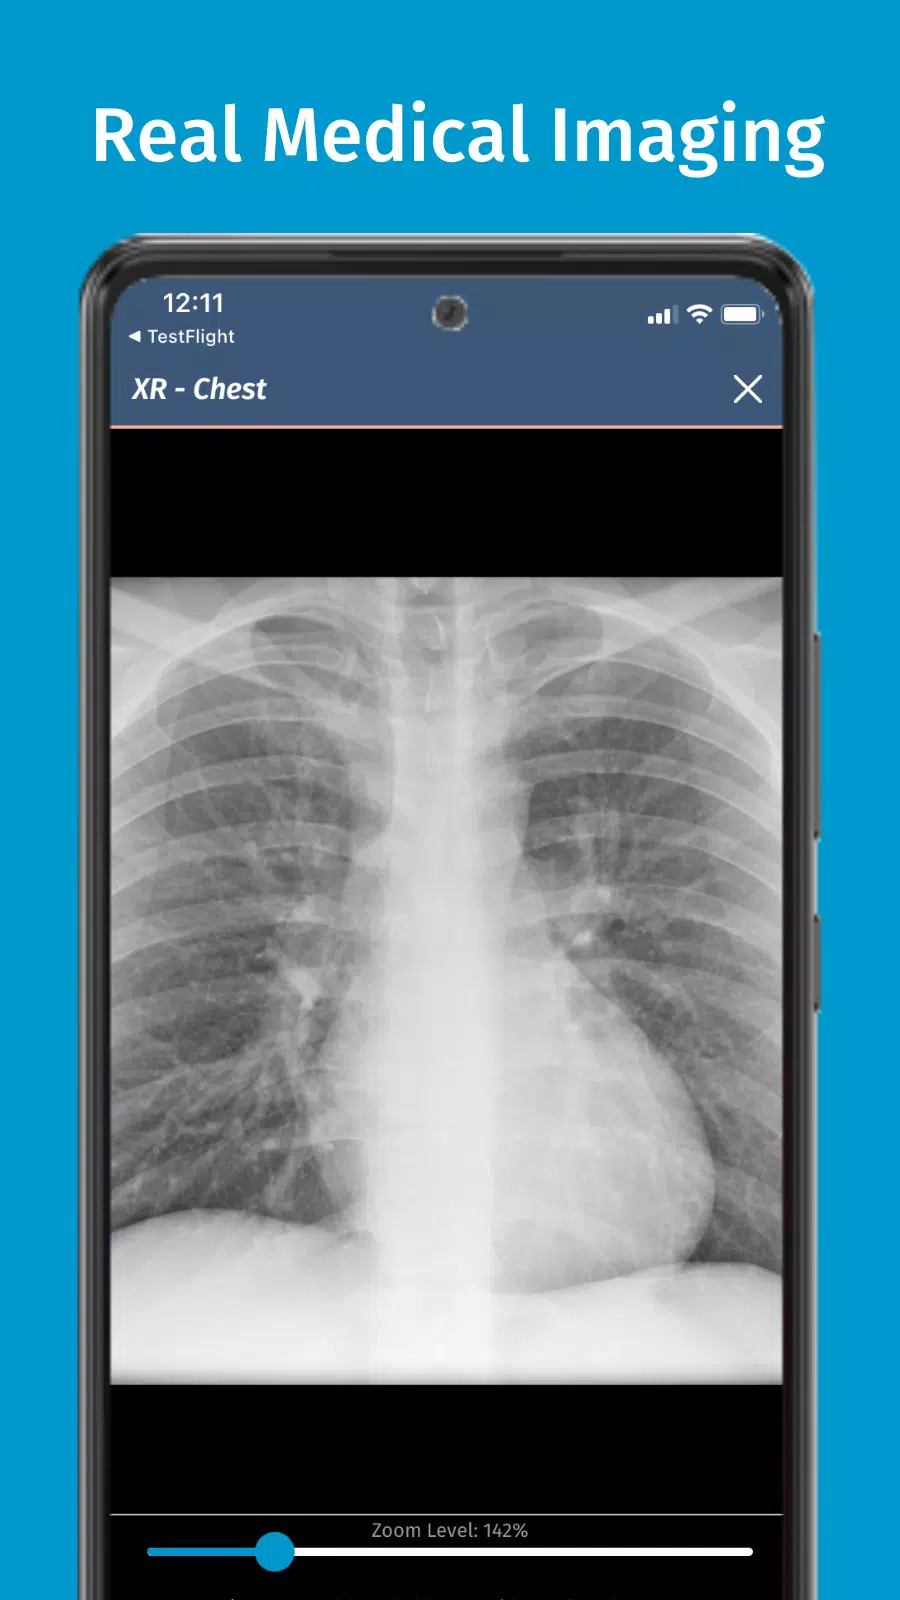

သွားအပေါ်ဆေးဘက်ဆိုင်ရာခြင်း simulation လေ့ကျင့်ပါ

ကုဒ်အပြည့်အဝ code ၏တောင်းဆိုခြင်းခြင်း simulation လေ့ကျင့်ရေးလေ့ကျင့်ရေးနှင့်အတူရှုပ်ထွေးသောဆေးဘက်ဆိုင်ရာကိစ္စရပ်များလေ့ကျင့်နိုင်ပြီးသင့်အားအခိုက်အတန့်ရှိသည့်အခါတိုင်းသင်၏ဆေးခန်းကျွမ်းကျင်မှုများကို Hone နိုင်သည်။ မိုဘိုင်းထုတ်ကုန်များအတွက်ဒီဇိုင်းရေးဆွဲထားသည့်ကုဒ်အပြည့်အ 0 သည်သင်ပိုင်ဆိုင်ပြီးသောကိရိယာများကို အသုံးပြု. သွားလာရန်နှင့်တိုးတက်ရန်ခွင့်ပြုသည်။